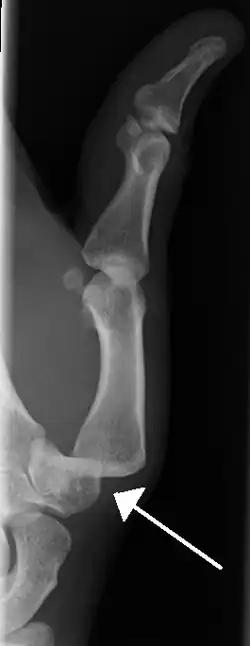

-

Dislocation of the left index finger -

Radiograph of right fifth phalanx bone dislocation -

Radiograph of left index finger dislocation